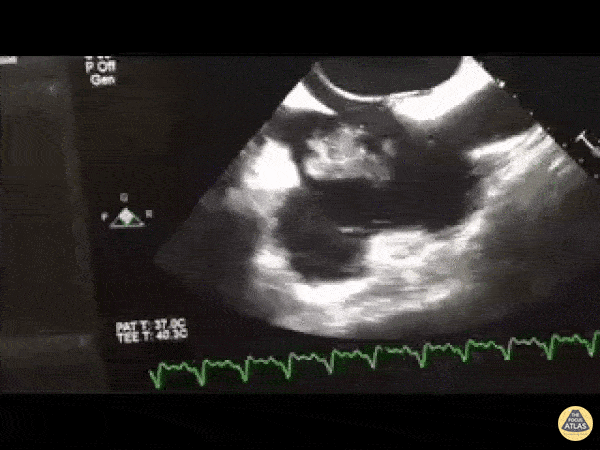

Patient in shock. TEE performed as TTE views not obtainable. Midesophageal bicaval view demonstrating what we've dubbed the "RA washing machine". WCUME 2017 Submission for "Best POCUS" Dr. Tom Jelic (@TomJelic) Winnipeg, Canada